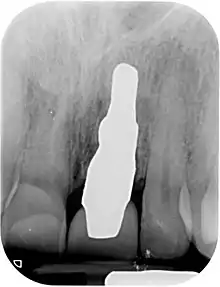

- Placement of the root analogue implant by tapping it in. In general, no surgery is necessary. In particular, no sinus lift or invasive surgery is ever necessary. The implant is placed immediately if it has been produced beforehand from a CBCT scan, or the next day if root has to be scanned or an impression of the socket is used. A protective splint is fitted to protect the implant during the healing period.

Recovery time is very fast as neither soft nor hard tissue is traumatized. Typically, even the day after implant placement there is no swelling, bruising or pain. After 8–12 weeks' healing period, the final crown may be fitted by a family dentist.